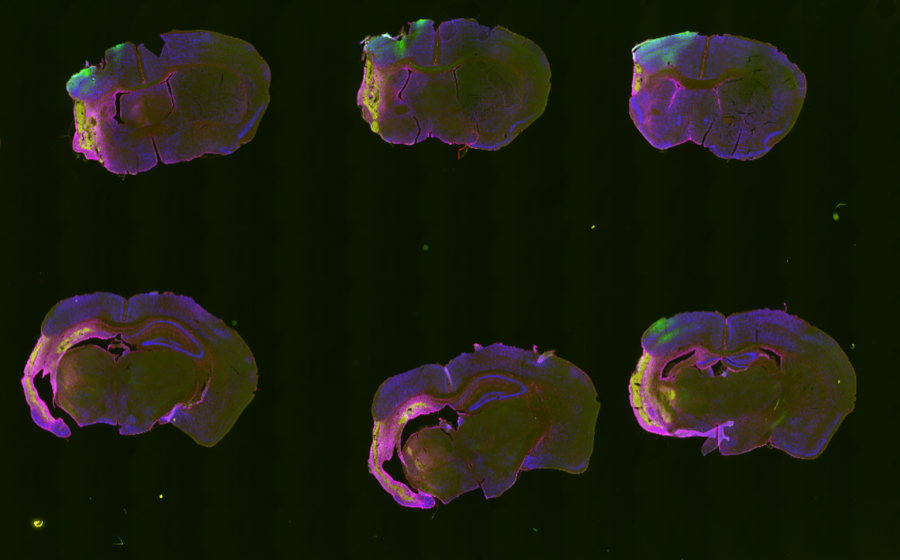

- Preprocess whole-slide IHC images into section-level analysis inputs.

Outputs

Analysis outputs include segmented infarct masks, merged review images, and CSV summaries saved per animal for quantitative comparison.